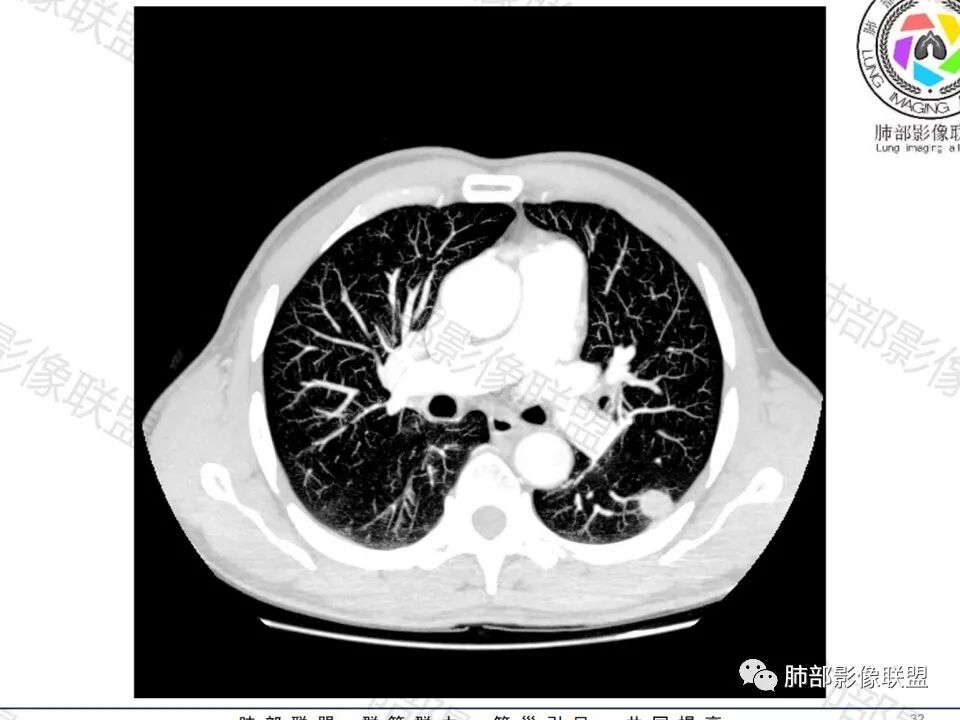

男,60体检发现左肺下叶结节,左肺下叶类圆形结节影,边界清晰,边缘见浅分叶及细短毛刺,病灶内见增粗血管影穿行,相应层面胸膜增厚,双肺另见微小结节影,增强扫描病灶轻度强化,考虑隐球菌,除外腺癌。

左肺下叶胸膜下实性小结节,边缘可见毛刺,轻度收缩,近端与血管束相连,远端轻度牵拉胸膜,并远端可见小空泡,平扫密度均匀,增强后渐近性强化,考虑腺癌,鉴别隐球菌

中老年男性患者,无症状体检发现,胸部CT:左下肺内前基底段近胸膜下类圆形结节,边缘清晰,周围晕征,周围毛刺细软,有胸膜牵拉及血管进入,增强扫描明显不均匀强化,考虑炎性肉芽肿,隐球菌可能,鉴别腺癌

左肺下叶胸膜下类圆形结节,边缘光滑,周围有晕,晕中有毛刺,周围可见小卫星灶,相邻胸膜增厚,血管进入,右肺中叶可见小结节影,考虑炎性肉芽肿,隐球菌。鉴别腺癌。

晨读:左肺下叶胸膜下实性小结节,边缘可见模糊晕及毛刺,轻度收缩,与支气管关系不清,近端与血管束相连,内见小空泡,平扫密度均匀,均匀强化。远近可见多个小结节。考虑炎性肉芽肿,隐球菌病,鉴别结核、腺癌。